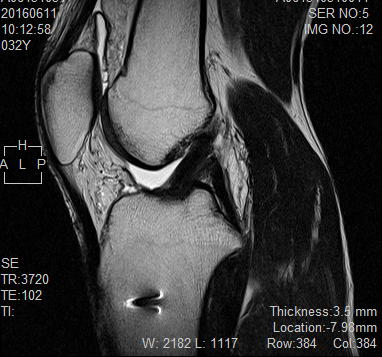

自宅に戻ってからパソコンで確認してみると、膝の周りの画像がずらっと並んでいます。素人なので細かいことはまったくわかりませんが、前回の手術で再建した靭帯らしき影がくっきりと写っているのが見えました。

画像の下のほうには、矢印のようなマークがいくつかついています。ここには、前回の手術で靭帯を固定するために入れているボルトがあるとのことでした。

「本当に脚の中にボルトが入っているんだな」と、改めて実感させられる瞬間でした。